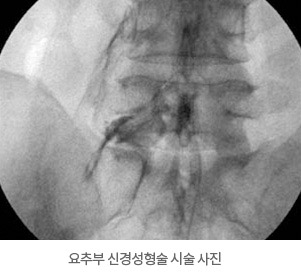

- └ 요추부신경차단술

허리 디스크